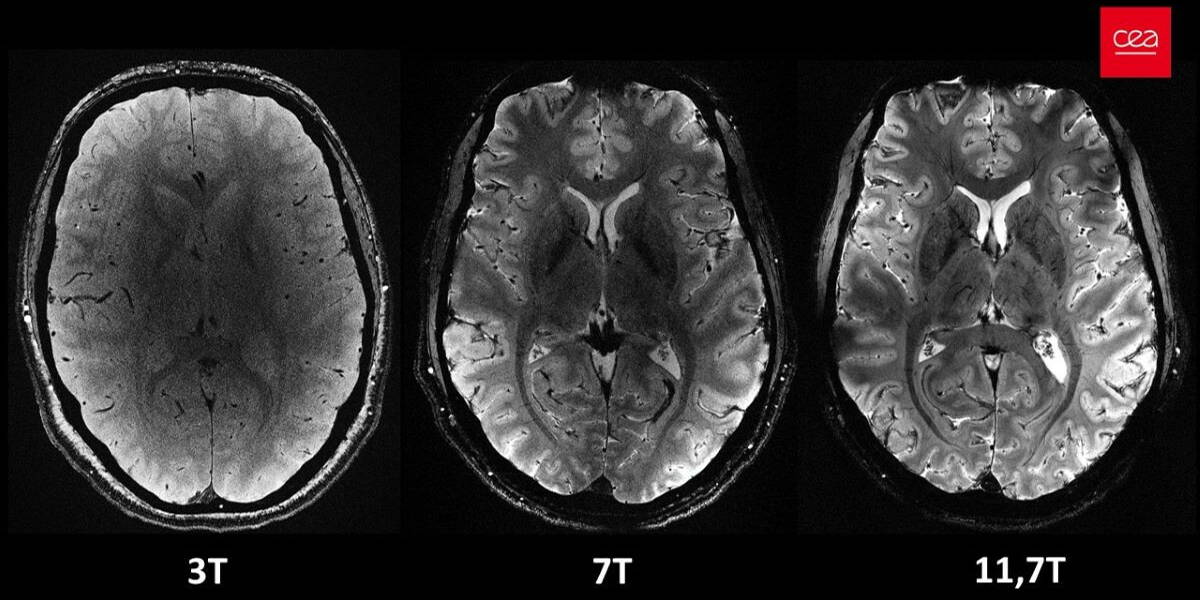

Het Commissariat à l'énergie atomique et aux énergies alternatives (CEA) is een toonaangevende Franse overheidsorganisatie die zich richt op onderzoek, ontwikkeling en innovatie. Opgericht na de Tweede Wereldoorlog, in 1945, speelt het CEA een grote rol in het bevorderen van wetenschappelijke kennis en het stimuleren van technologische ontwikkeling in Frankrijk en daarbuiten. De organisatie presenteert nu de Iseult MRI-scanner. Deze bleek in staat om in vier minuten tijd de meest indrukwekkende anatomische hersenbeelden ooit te produceren. Met 11,7 Tesla overtreft de machine de huidige ziekenhuisscanners (1,5 of 3 tesla), niet alleen op het gebied van snelheid maar ook in het geven van details in de beelden.

Ongelooflijke hersendetails

Op de scans van de hersenen zijn ongelooflijke details zichtbaar tot wel 0,2 millimeter, waaronder zeer fijne bloedvaatjes in het brein. Het detailniveau is indrukwekkend, want reguliere scanners hebben een resolutie van ongeveer 1 millimeter. De grote mate van detail geeft nieuwe inzichten in de anatomie, verbindingen en activiteit van de hersenen. Het stelt onderzoekers in staat om fundamentele vragen over hersenmechanismen te beantwoorden. Bovendien opent het nieuwe onderzoeksmogelijkheden naar de diagnose en behandeling van neurodegeneratieve ziekten zoals Alzheimer en Parkinson. Tot slot biedt deze krachtige machine aanknopingspunten voor toekomstige studies, die kunnen helpen om de effectiviteit van medicijnen, zoals lithium voor bipolaire stoornissen, beter te begrijpen.